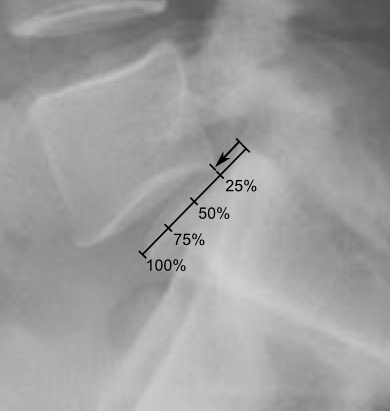

척추전방전위증의 엑스레이(x-ray) 촬영 이미지